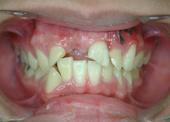

圖五、 右上犬齒長不出來

圖六、經過手術及矯正牽引

導致牙齒排列不整的原因包羅萬象,情況也是千奇百怪。有的人是因為牙齒大小和牙床大小不諧調,導致齒列擁擠(圖一、二)或是產生縫隙,台灣人最介意的“牙齒漏財”即屬於縫隙這個類型(圖三、四);有的人則是牙齒長到不該長的位置而沒有冒出牙床(圖五、六);有些人則是上下顎骨發育不諧調,導致戽斗(或稱月亮臉)或是鳥臉的狀況;除此之外,暴牙、先天缺牙、多生牙、後天蛀牙或長期缺牙導致相鄰牙齒東倒西歪、車禍外傷導致牙齒移位或喪失牙齒(圖七、八)、牙周病所導致的門牙散開…等等,都是齒顎矯正的適應症。